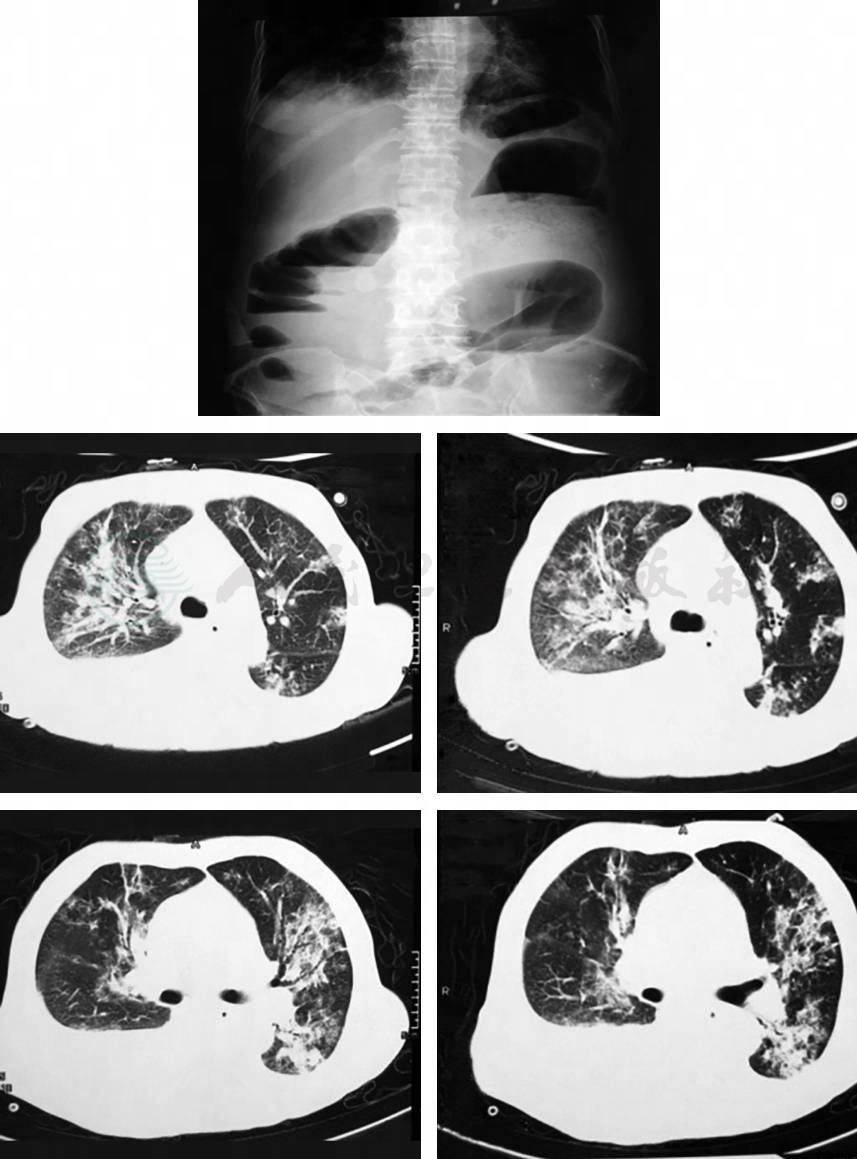

血常规:白细胞计数25.55×109/L,中性粒细胞占比0.846 4,血小板计数337×109/L,ALB 22g/L,大便常规基本正常。立位腹部X线平片(图1)示肠管积气,可见液气平。胸部及腹部CT检查(图2)示肺感染,胸腔、腹腔及心包积液。

图1 立位腹部X线平片(2015-02-21)

图2 胸部及腹部CT(2015-02-21)

老年女性患者,因“间断腹胀伴呕吐半年,腹泻腹痛2d”入院。实验室检查:血常规,白细胞计数25.55×109/L,中性粒细胞占比0.846 4,血小板计数337×109/L,ALB 22g/L;大便常规基本正常。立位腹部X线平片示肠管积气,可见液气平。胸部及腹部CT检查示肺感染,胸腔、腹腔及心包积液。